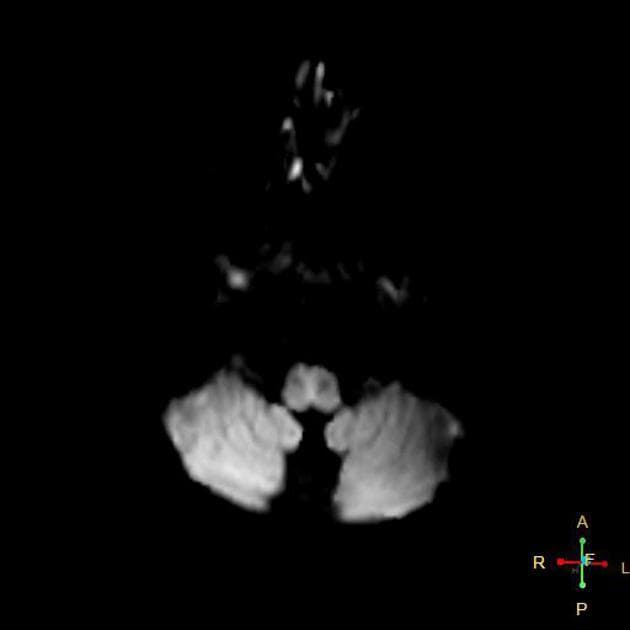

Hai mảng xơ vữa (plaque) khác được thấy ở phần thân não bên trái, tại hành não (medulla oblongata) và cầu não (pons).

Các tổn thương tại hành não bên trái và cầu não cũng rõ ràng trên hình ảnh.